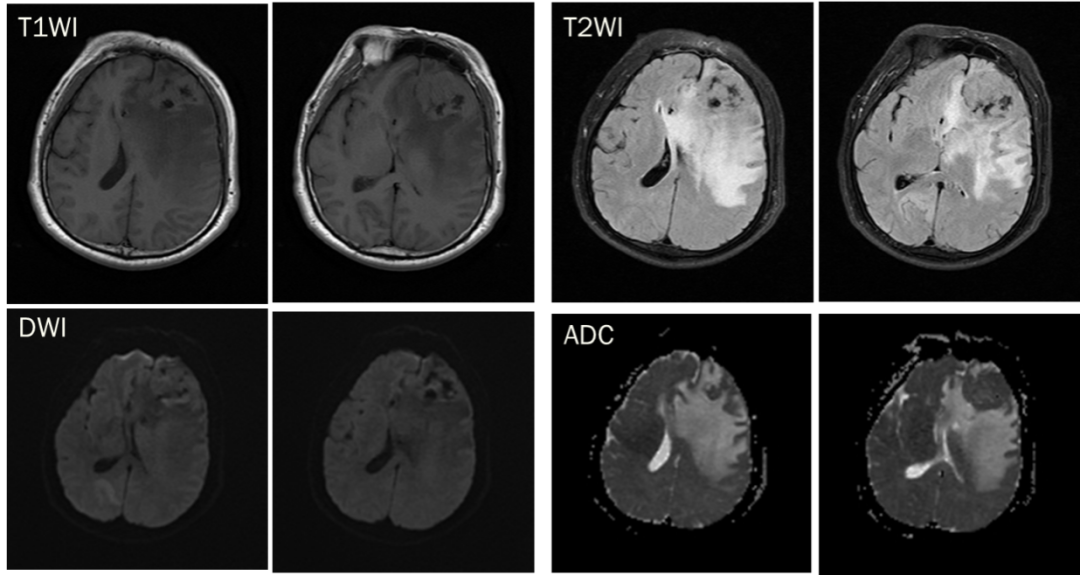

CASE 1

男,58 岁

CT 平扫:左侧额部占位,内伴钙化,周围见半片状水肿,大脑镰向右侧移位,邻近骨质未见破坏。

T1WI 呈等低信号,T2WI 实性成分呈等高信号,DWI 信号未见增高,ADC 值未见减低,增强实性成分明显强化,中央低信号钙化成分未见强化。邻近脑膜增厚(红箭头),脑膜尾征。

诊断:左侧额部脑膜瘤